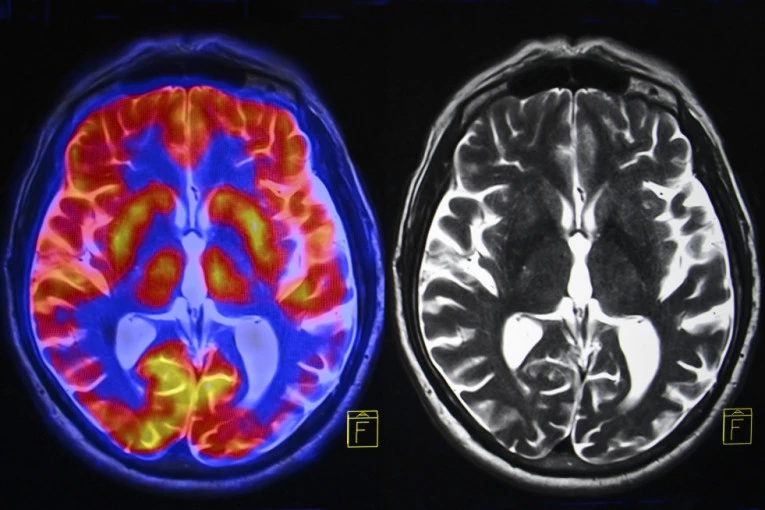

CT i MRI snimci otkrili su prisustvo cisti u mozgu, a dijagnoza je bila neurocisticerkoza, parazitska infekcija koja može nastati konzumiranjem zaraženog mesa. Lekari veruju da je parazit ušao u telo pacijenta nakon konzumiranja nedovoljno pečene slanine i putovao iz creva do mozga krvotokom, piše "Miror".